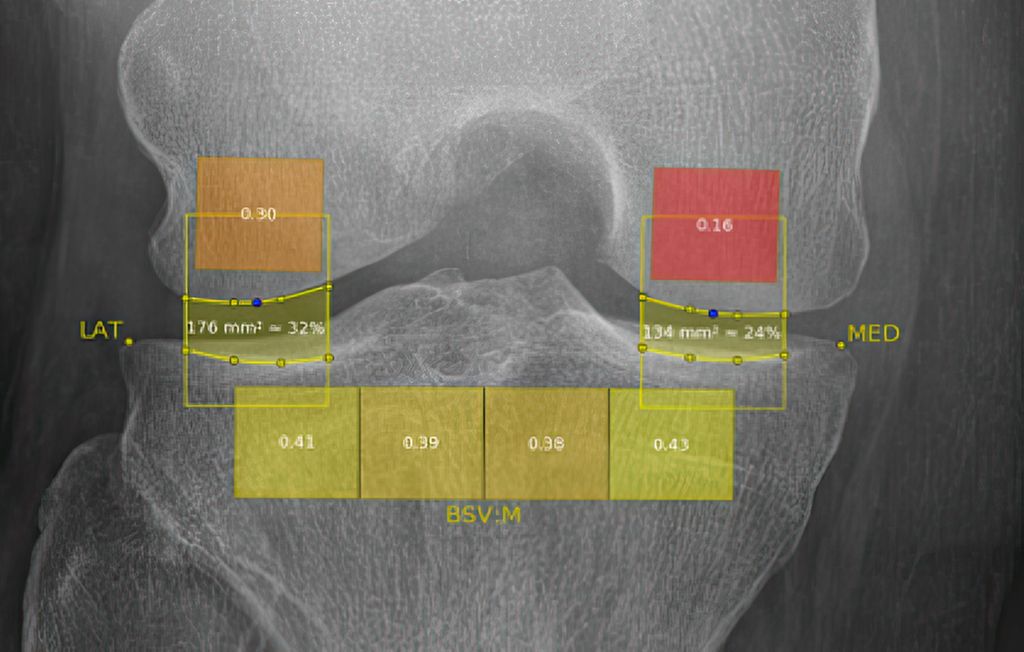

Dem Prozess der Degeneration des Gelenkknorpels, der mit der OA einhergeht, gehen subtile Veränderungen der trabekulären Knochenstruktur und die Bildung von neuem Knochen an den Gelenkrändern, den sogenannten Osteophyten, voraus. Es wurde nachgewiesen, dass Veränderungen der trabekulären Knochenstruktur im subchondralen Knochenkompartiment des Schienbeins bereits Monate bis Jahre vor den nachweisbaren Veränderungen der Gelenkknorpeldicke auftreten. Infolgedessen war der Zusammenhang der radiologischen OA-Progression und -Inzidenz mit der Analyse der trabekulären Struktur des Tibiakopfes im Fokus der Forschung. Die Mehrheit der Studien untersucht die mathematische fraktale Architektur der Knochentextur des subchondralen Teils des Tibiakopfes, die aus Röntgenaufnahmen gewonnen wird. Die Anwendung fraktaler Analysen für die Analyse der subchondralen Knochenmikroarchitektur basiert auf der Tatsache, dass die auf einfachen Röntgenaufnahmen erkennbare trabekuläre Knochentextur direkt mit der zugrunde liegenden dreidimensionalen trabekulären Knochenstruktur korreliert wurde. In dieser mathematischen digitalen Analyse ergibt sich ein sogenannter „bone structure value“ (BSV), der sich in KI(künstliche Intelligenz)-Algorithmen als Parameter der Prognose des Fortschreitens und Auftretens von OA trainieren lässt. Der BSV misst die fraktale Dimension der Knochentextur mittels Hurst-Koeffizient, der ein Maß für die weiträumige Abhängigkeit von Datenpunkten (Pixel) ist und damit ein Parameter der Entropie (Strukturregelmäßigkeit) des Gewebes, und zeigt damit früher Veränderungen der Mikrostruktur des Knochens an, die mit dem bloßen Auge nicht erkennbar sind.

Bedeutung von Veränderungen in der subchondralen Knochenstruktur

Unsere Ergebnisse deuten darauf hin, dass die computergestützte Auswertung digitaler Röntgendaten frühe Veränderungen in der subchondralen Knochenstruktur qualifiziert und quantifiziert und einige Rückschlüsse auf die OA-Entwicklung und -Prognose zulässt. Die prospektive Anwendung und Weiterverfolgung einer solchen Röntgenbeurteilung und einfach zu bedienenden Softwaretechnologie werden dazu beitragen, objektive Ergebnisse für OA-Studien zu schaffen und auch in der Patientenberatung besonders Patient:innen mit einem hohen Arthroseprogressionsrisiko intensiv zu beraten und zu behandeln.